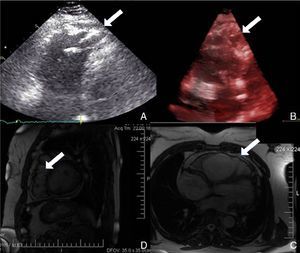

Physical examination showed no abnormalities. Diagnostic exams included 12-lead electrocardiogram (ECG), which showed a pattern of right bundle branch block, together with epsilon waves and T-wave inversion in leads V1–V3 (Figure 1). In order to characterize the typical ARVC alterations, a right-sided precordial lead ECG and a modified Fontaine ECG were performed, the latter with the following placement of electrodes: the right arm electrode over the manubrium, the left arm electrode over the xiphoid and the left leg electrode in the area corresponding to V4, at a recording speed of 25 mm/s and voltage of 10 mm/mV (Figure 2). Both methods clearly showed epsilon waves, especially the modified Fontaine ECG (Figure 3A and B). Two- and three-dimensional transthoracic echocardiography at our institution showed severe right ventricular dilatation and hypokinesia, with prominent apical trabeculae and false tendons and saccular dilatations in the ventricular free wall (Figure 4A and B). Cardiac magnetic resonance imaging revealed small foci of subepicardial fatty infiltration in the right ventricular free and inferior walls, interventricular septum and left ventricular free wall; late enhancement study showed focal enhancement in the interventricular septum consistent with fibrosis (Figure 4C and D).

Since the patient remained asymptomatic and 24-hour Holter monitoring showed only pairs and a triplet of ventricular extrasystoles, therapy with amiodarone 200 mg daily was begun and follow-up was scheduled. Around a year later, following an episode of fainting, nonsustained ventricular tachycardia (VT) was documented, with a pattern of left bundle branch block and superior axis (Figure 3C). This situation, besides being a major criterion for a diagnosis of ARVC, prompted placement of an ICD; around a month after implantation, an episode of VT was converted to sinus rhythm with an appropriate shock following unsuccessful antitachycardia pacing. Around 18 months after this episode, there has been no recurrence of ventricular arrhythmias.